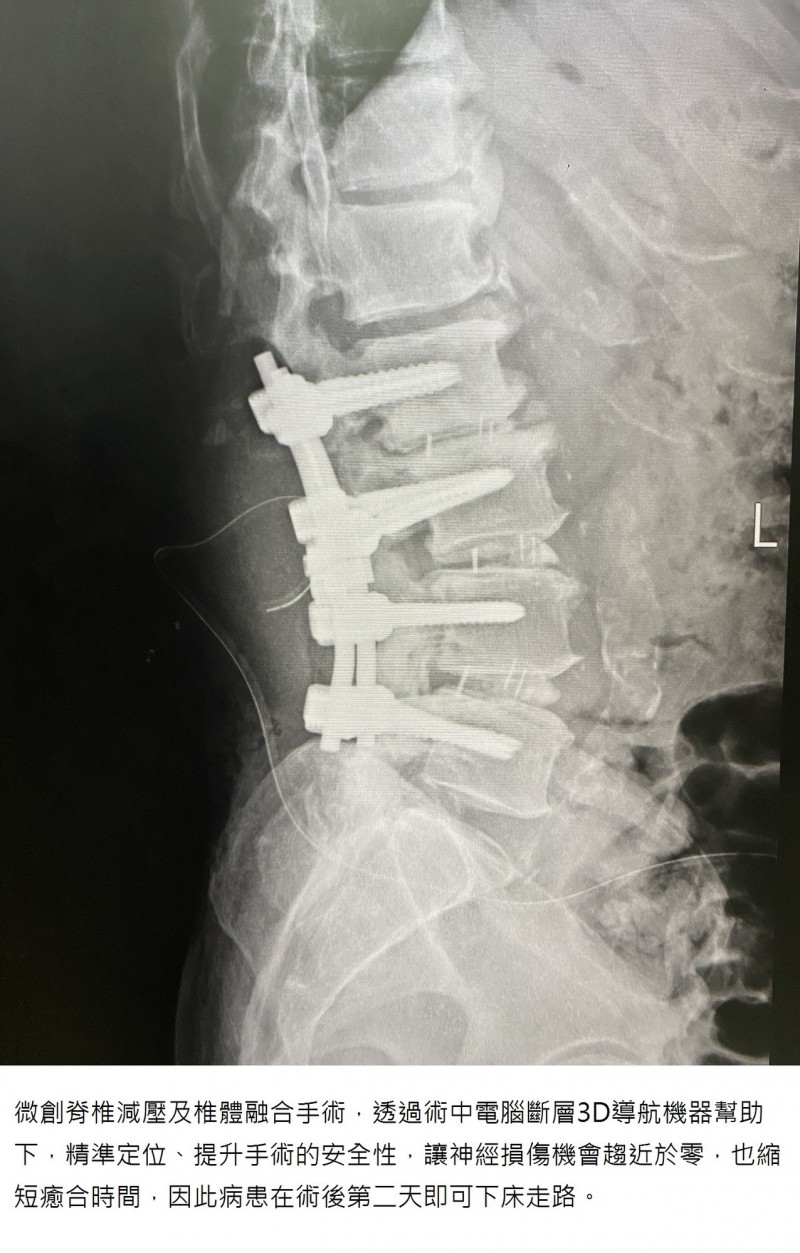

對於這門快速見效的新型手術,楊醫師也分享它與傳統手術的差別,「傳統的椎體融合手術,是靠X光機做判斷因此神經損傷風險高...」但現在的新型微創脊椎減壓及椎體融合手術,「是在術中電腦斷層3D導航機器幫助下,能精準定位、提升手術的安全性,讓神經損傷機會趨近於零,也縮短癒合時間,因此病患在術後第2天即可下床走路!」